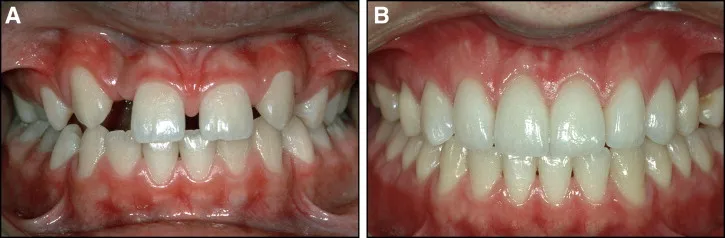

Le traitement des agénésies bilatérales des incisives latérales supérieures repose sur deux grandes options thérapeutiques, chacune présentant des variantes. Une concertation étroite entre l’orthodontiste et le dentiste prothésiste est essentielle pour déterminer la meilleure approche en fonction des caractéristiques cliniques du patient.

Option 1 : Conservation ou Augmentation des Diastèmes pour les Incisives Latérales

Option 2 : Déplacement des Canines en Position d’Incisive Latérale avec Fermeture des Diastèmes Antérieurs

- Finition esthétique : Reconstitution des angles des dents à l’aide de composites chargés.